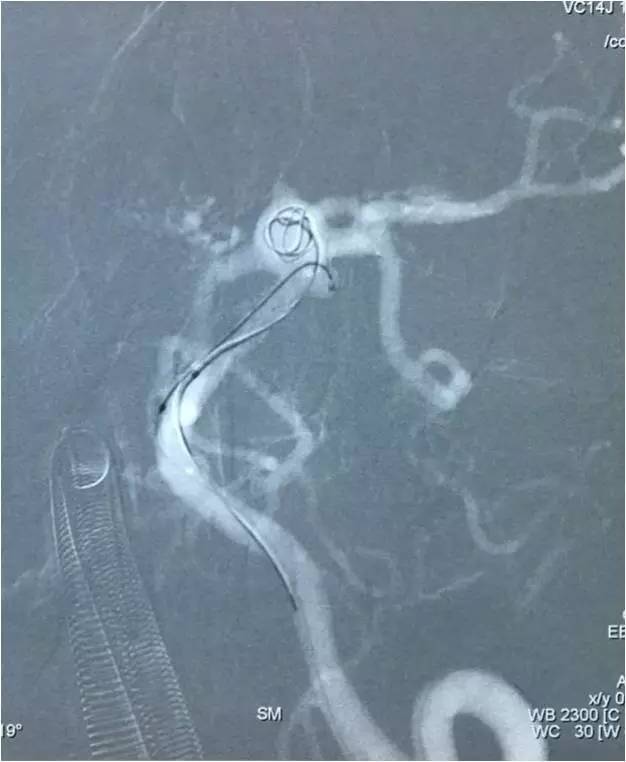

▼空白路图填圈,惊喜地发现圈进入子瘤了,这是侧位空白路图。

▼这是正位空白路图,充分显示了双C臂的优势。

▼乘胜追击,子瘤被完全填满,这是侧位蒙片。

▼这是正位蒙片,子瘤被填塞,术者心里才踏实。

下面是术后各个角度的左椎动脉造影,可见基底动脉顶端动脉瘤和左小脑上动脉瘤完全栓塞,载瘤动脉畅通。基底动脉顶端动脉瘤的子瘤终于被消灭。